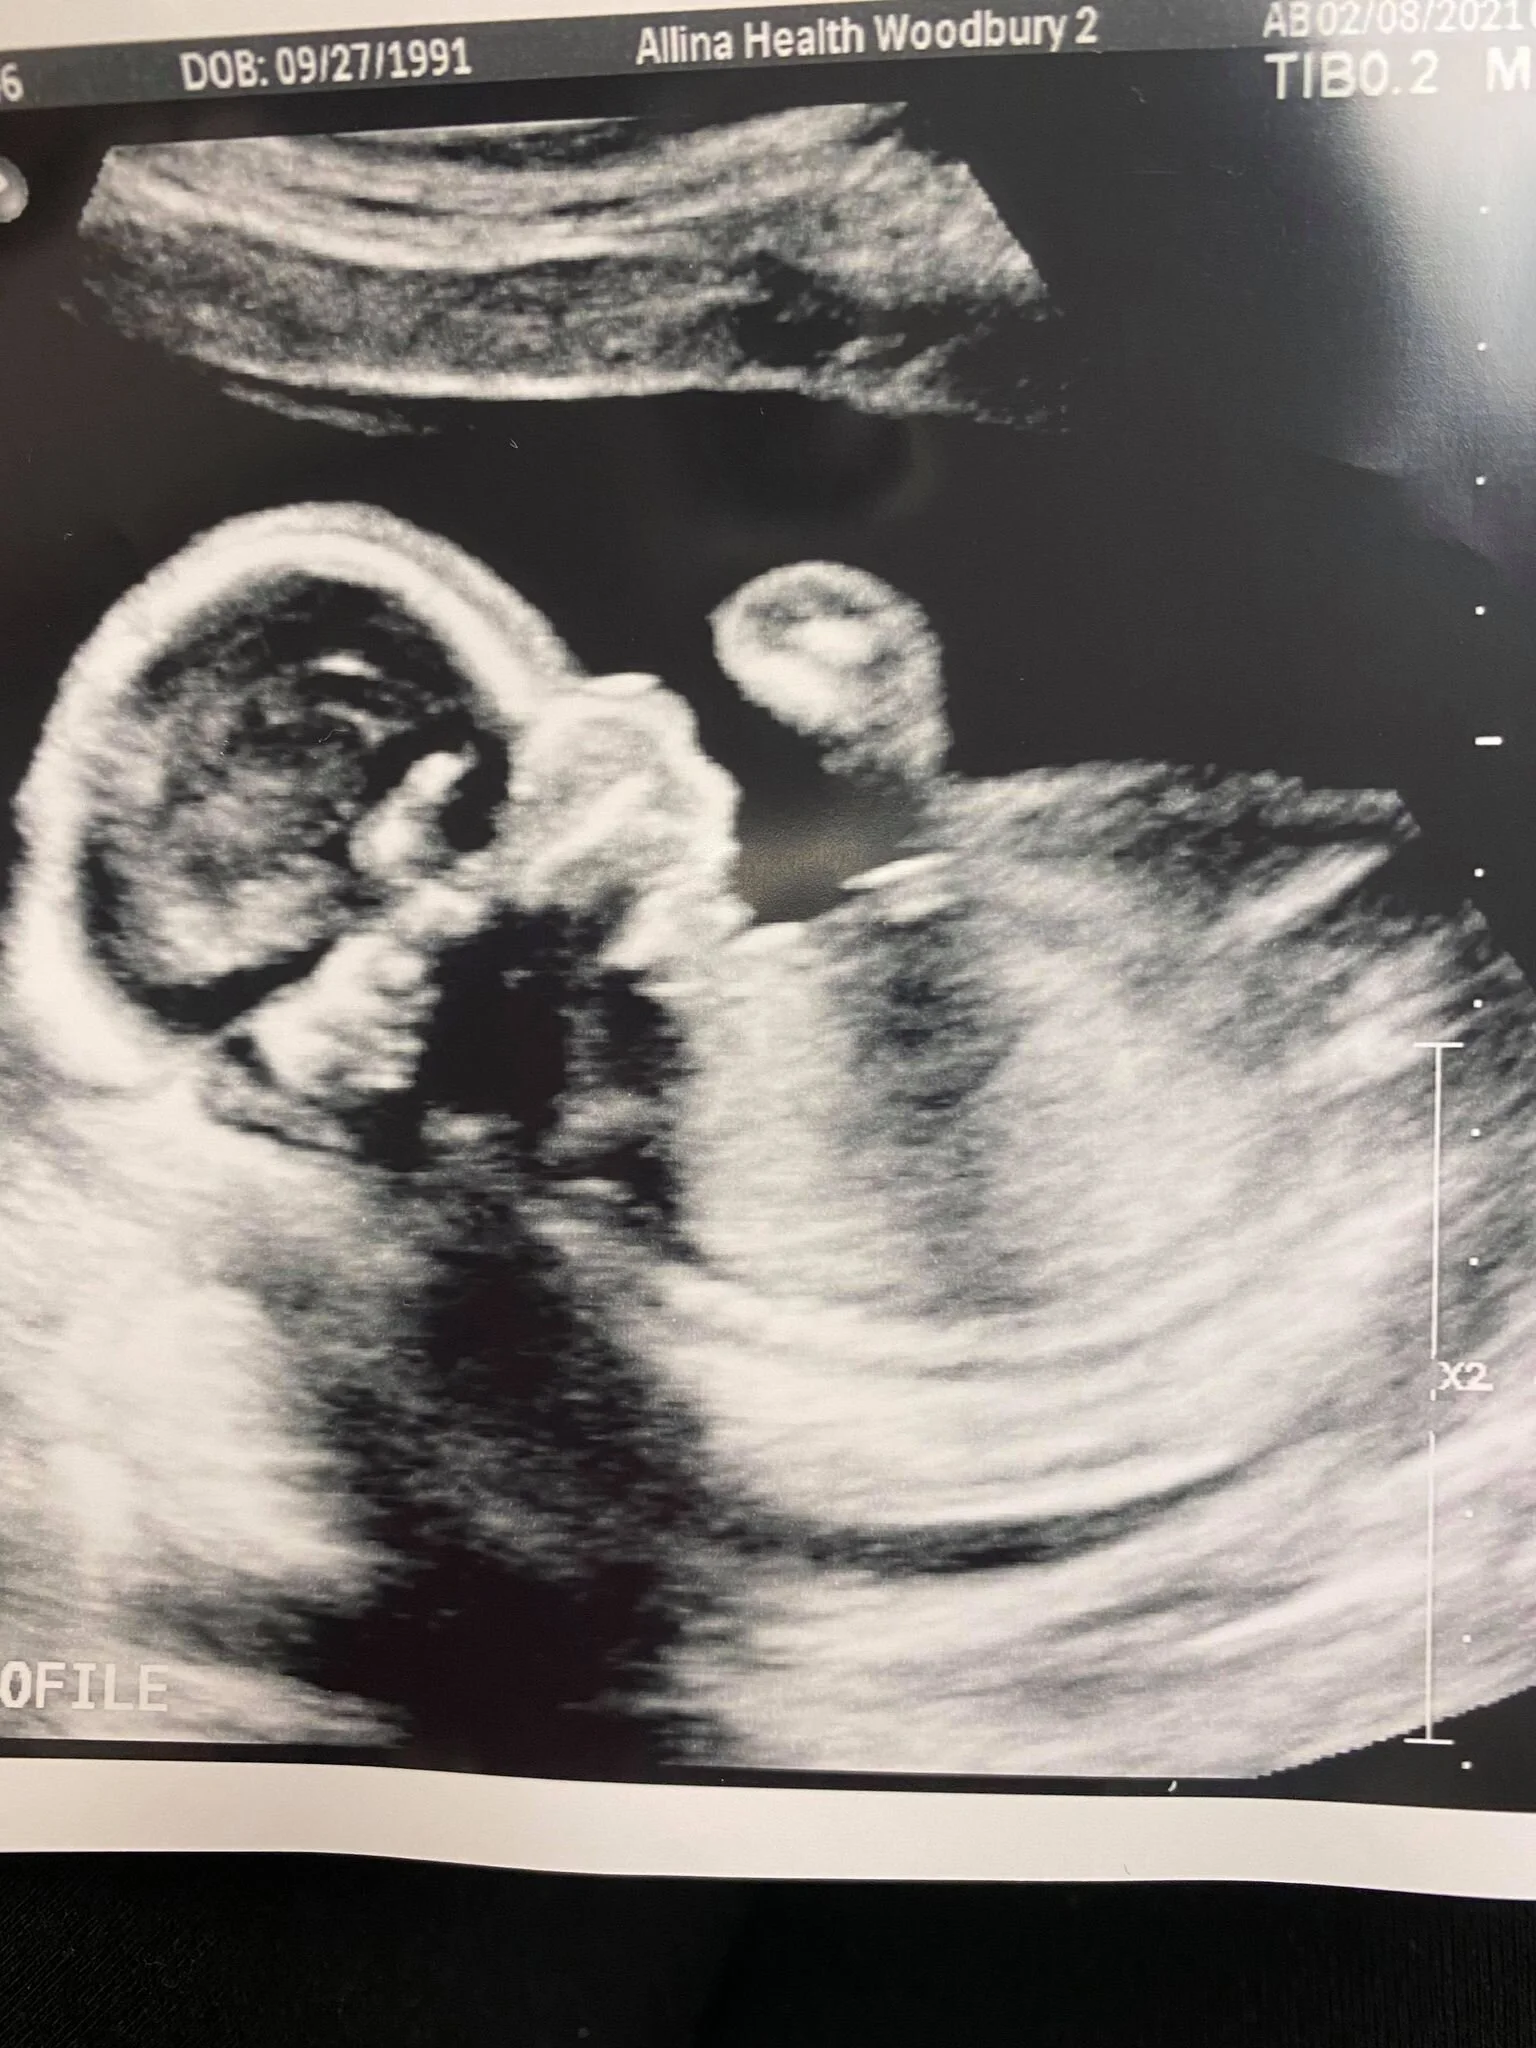

So as many of you already know, we are expecting our third little babe at the end of June. Below I’ll share how we found out we were expecting, all about the gender, and how this pregnancy is compared to my other two.

This pregnancy has been sooo much different than the boys. I was never really sick with the boys and my whole first trimester with this little one was rough. My scent was on fire with just about everything and I couldn’t keep things down. From throwing up in the mornings to having terrible nausea in the evenings. Also, my acne has been awful!! My hormones have been all over the place so my chin has been looking rough. Luckily this second trimester has been better overall. There are still some nights I don’t feel too well or certain foods don’t sit well but overall feeling good. I have stayed active throughout the pregnancy so far, which I truly think helps my body and mood overall. I am now 6 months pregnant and definitely am slowing down. My belly somehow seems to look like I’m 8 months pregnant and each night I am dead by like 8pm! The boys keep me on my toes all day, which is tough in general. plus with carrying around the extra weight. It is hard to go through these body changes but I have to remind myself that it is helping create life and I can do anything for 9 months! I feel ugly some days and I know some women thrive and love being pregnant, which has never been me (mostly because I don’t like slowing down), but I know that God puts us each in a position for a reason so I try and embrace it the best I can!